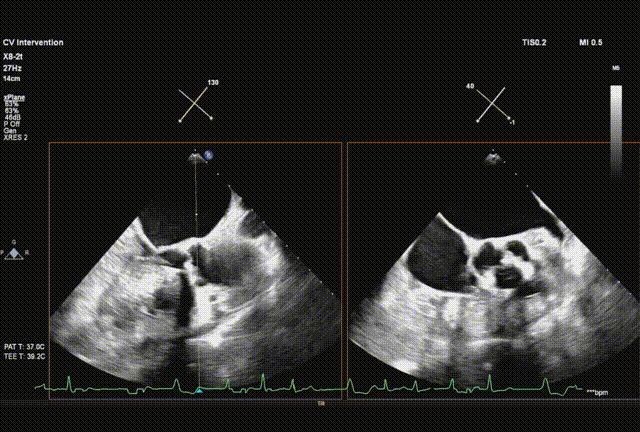

瓣膜初始释放到喇叭状形态并定位植入深度

采样线扫到无窦,180起搏,长轴视图下快速释放到工作位

超声从左至右,最后无冠窦侧评估深度合适

起搏下完全释放瓣膜

左右旋转系统并前送,观察无瓣膜移动,回撤导丝后再撤出系统

术后超声评估,未见瓣周漏,平均跨瓣压15 mmHg,血流速度197 cm/s